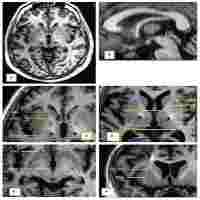

| Abstract | Background We sought to analyze, in well-defined clinical setting, the first 100 patients treated at the intraoperative MRI (iMRI) hybrid surgical theatre at our facility in a population-based setting to evaluate which pathologies are best approached with iMRI assisted surgeries, as this is not yet clearly defined. Methods Patients undergoing surgery in the 3T iMRI hybrid surgical theatre at our neurosurgical department between December 2017 to May 2021 were included after informed consent. Demographic, clinical, surgical, histological, radiological and outcome parameters, as well as variables related to iMRI, were retrospectively collected and analyzed. Patients were subdivided into adult and pediatric cohorts. Results Various neurosurgical procedures were performed; resection of tumors and epileptic foci, endoscopic skull base procedures including pituitary lesions, deep brain stimulation (DBS) and laser interstitial thermal therapy (LITT). In total, 41 patients were pediatric. An iMRI scan was carried out in 96% of cases and led to continuation of surgery in 50% of cases, mainly due to visualized remaining pathological tissue (95.2%). Median time to iMRI from intubation was 280 min and median total duration of surgery was 445 min. The majority of patients experienced no postoperative complications (70%), 13 patients suffered permanent postoperative deficits, predominantly visual. Conclusion Herein, we demonstrate the first 100 patients undergoing neurosurgery aided by iMRI at our facility since introduction. Indications for surgery differed between pediatric and adult patients. The iMRI was utilized for tumor surgeries, particularly adult low-grade gliomas and pediatric tumors, as well as for epilepsy surgery and DBS. In this heterogenous population, iMRI led to continuation of surgery in 50%. To establish the benefit in maximizing the extent of resection in these brain pathologies future studies are recommended. Clinical trial number Not applicable. |